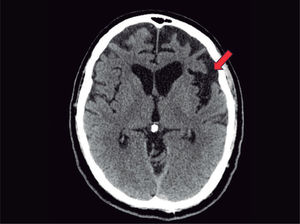

En la resonancia magnética, se visualiza una atrofia de las sustancias gris y blanca frontotemporal.